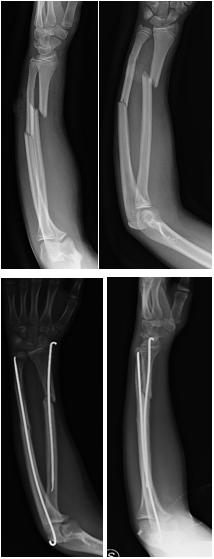

Fratture di avambraccio, fratture diafisarie

Rappresentano il 15% circa delle fratture di avambraccio.

Nelle fratture incomplete (a “legno verde” e deformazioni plastica) il trattamento è incruento mediante applicazione di apparecchio gessato. Quando è presente un'angolazione >10° e nei pazienti di età superiore ai 10 anni è necessario correggere (ideale una lieve ipercorrezione) l'angolazione con delicata manovra riduttiva.

Le fratture scomposte sono suddivise in base alla rima di frattura in oblique, trasverse e comminute. Il trattamento conservativo in queste fratture può essere molto impegnativo per la presenza di masse muscolari che esercitano forze angolari e di rotazione sui frammenti di frattura e per interposizione di tessuto periostale.

Nei pazienti di età inefriore ai 10 anni le capacità di rimodellamento diafisarie permettono di tollerare un accorciamento di 1 cm, fino a 15° di angolazione e anche una completa perdita di contatto corticale. La tolleranza decresce per le fratture del terzo prossimale.

Il trattamento elettivo è incruento mediante riduzione in narcosi finalizzate a ottenere un ripristino dell'asse e un affrontamento dei monconi del 50-70%. Il gesso viene rinnovato periodicamente per una immobilizzazione complessiva di 8-12 settimane.

Il trattamento chirurgico viene riservato alle fratture esposte di 2°-3° grado, ai casi in cui la riduzione è inadeguata in relazione al potenziale di rimodellamento residuo, quando si verifica una perdita progressiva di riduzione in gesso (pattern di frattura più instabili), alle rifratture.

Nell'età pediatrica la sintesi viene realizzata tramite inchiodamento endomidollare con fili di Kirschner. In casi estremamente selezionati sono utilizzate placche e viti.